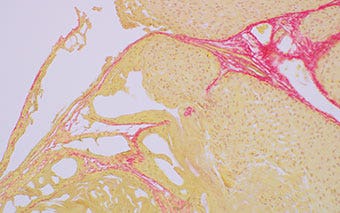

Tejido de pulmón de ratón (con tinción de rojo sirio)

Observación de campo claro

Observación de luz polarizada sobre un fondo negro con atenuación

Los tipos de colágeno I y III pueden ser detectados mediante el color naranja y verde, respectivamente.

Figura 1: Lámpara halógena de 100 W

Figura 2: Microscopio BX53 equipado del LED de alta reproducción de color y luminosidad